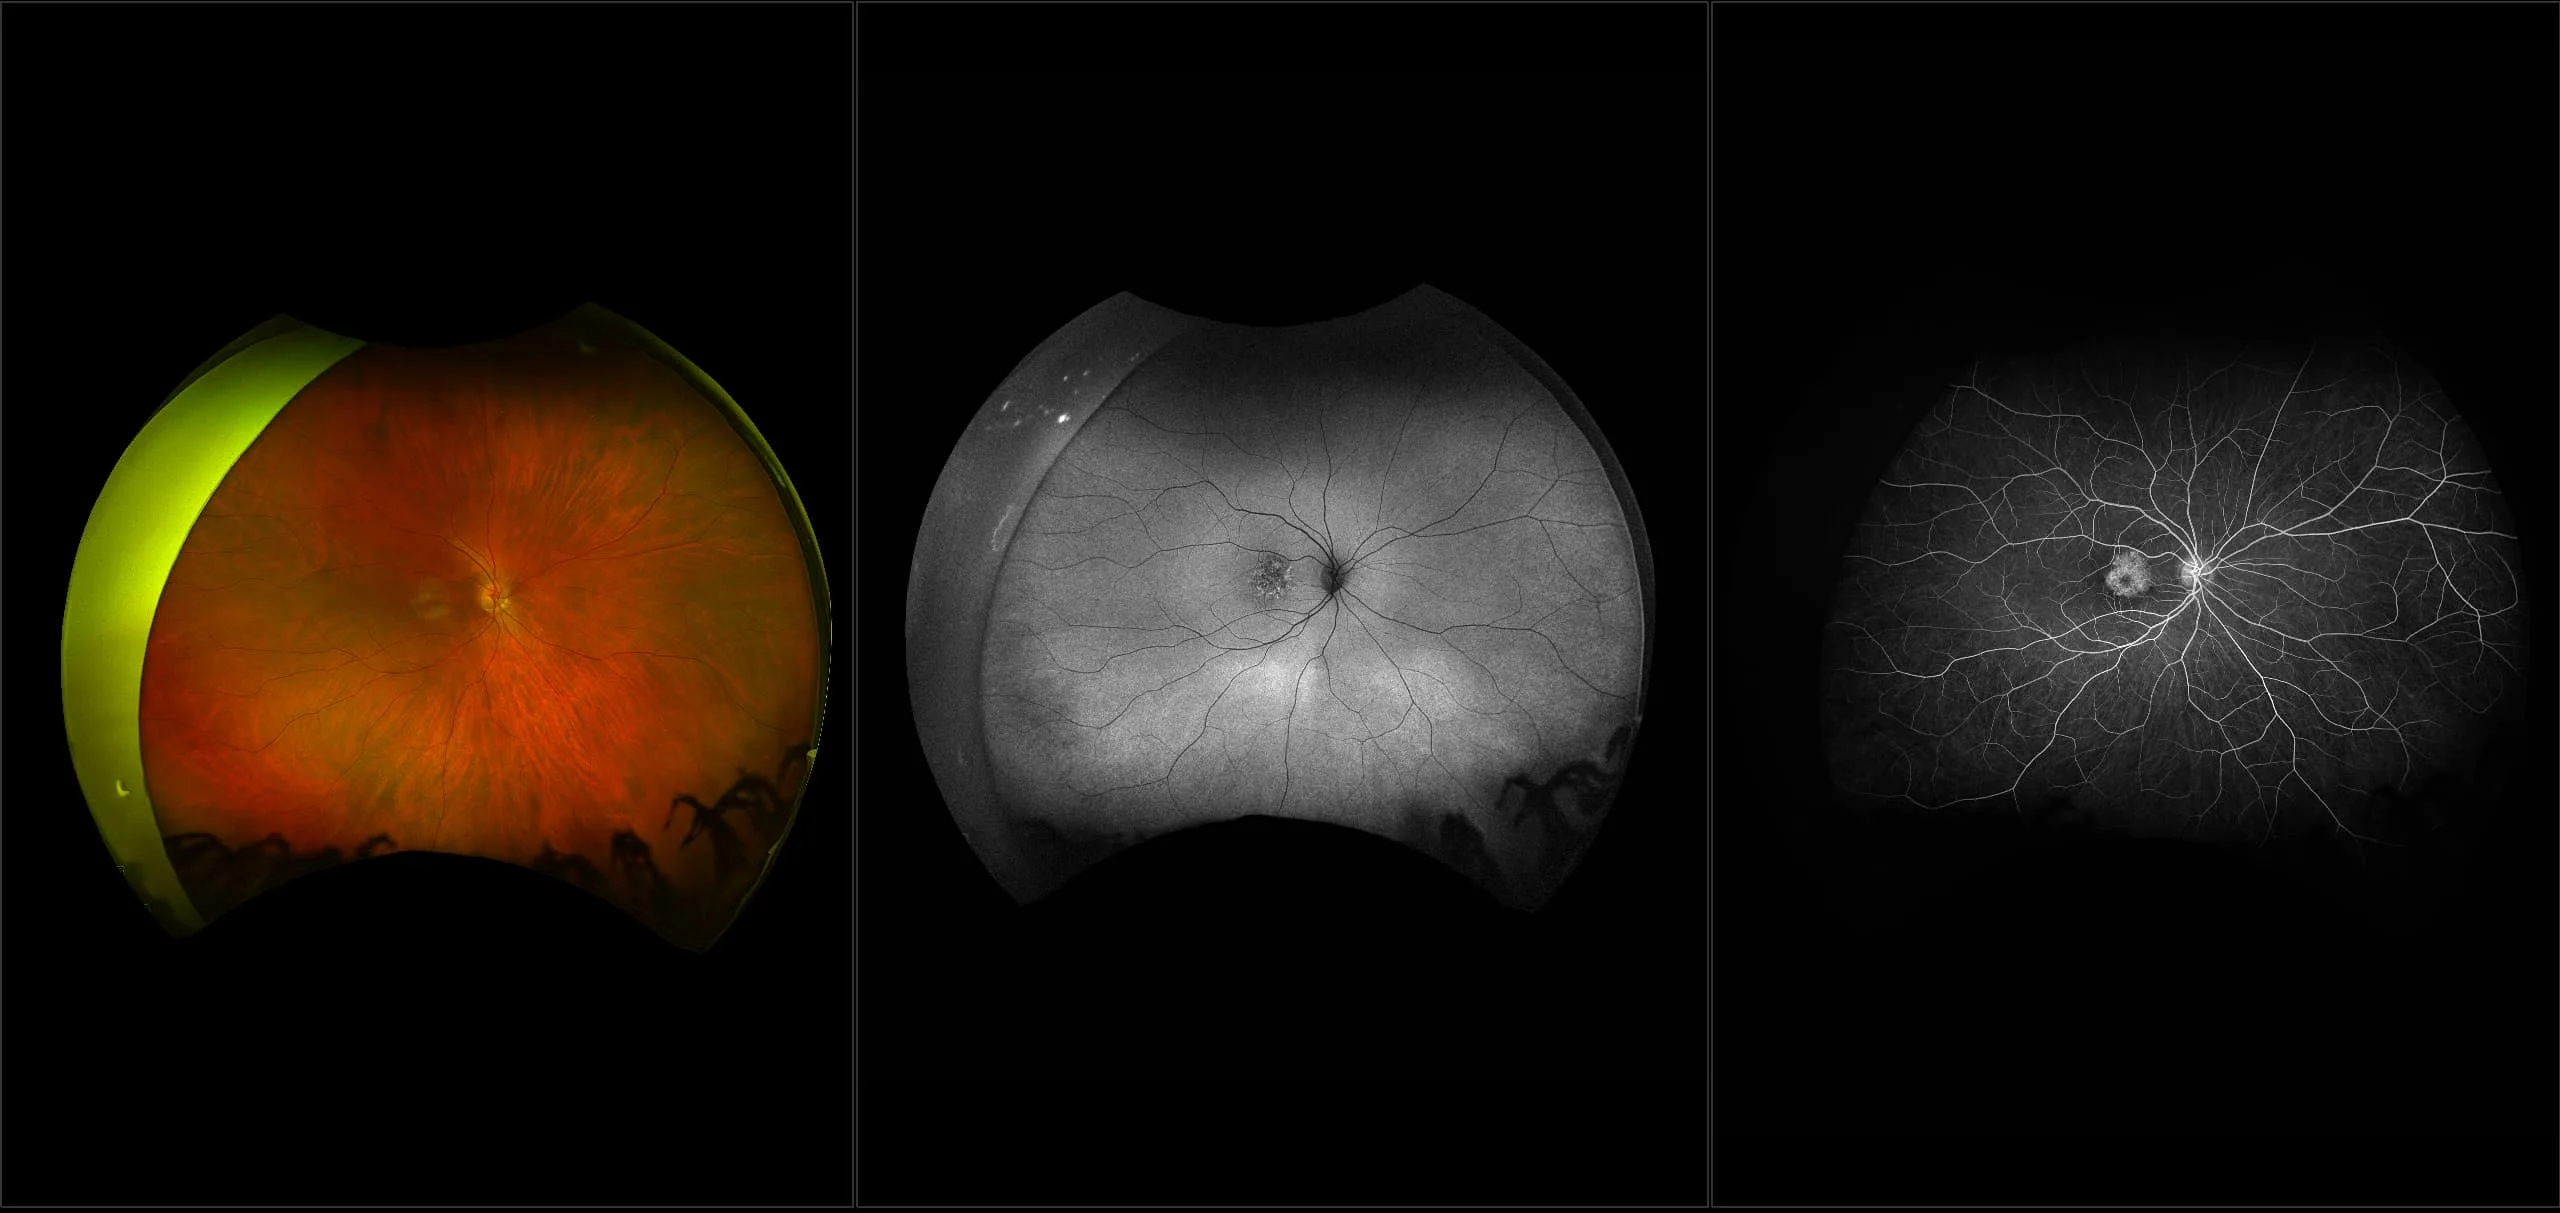

MonacoPro - Vitreous Floaters, RG, OCT

Vitreous floaters are microscopic collagen fibers within the vitreous that tend to clump and cast shadows on the retina, appearing as floaters to the patient.